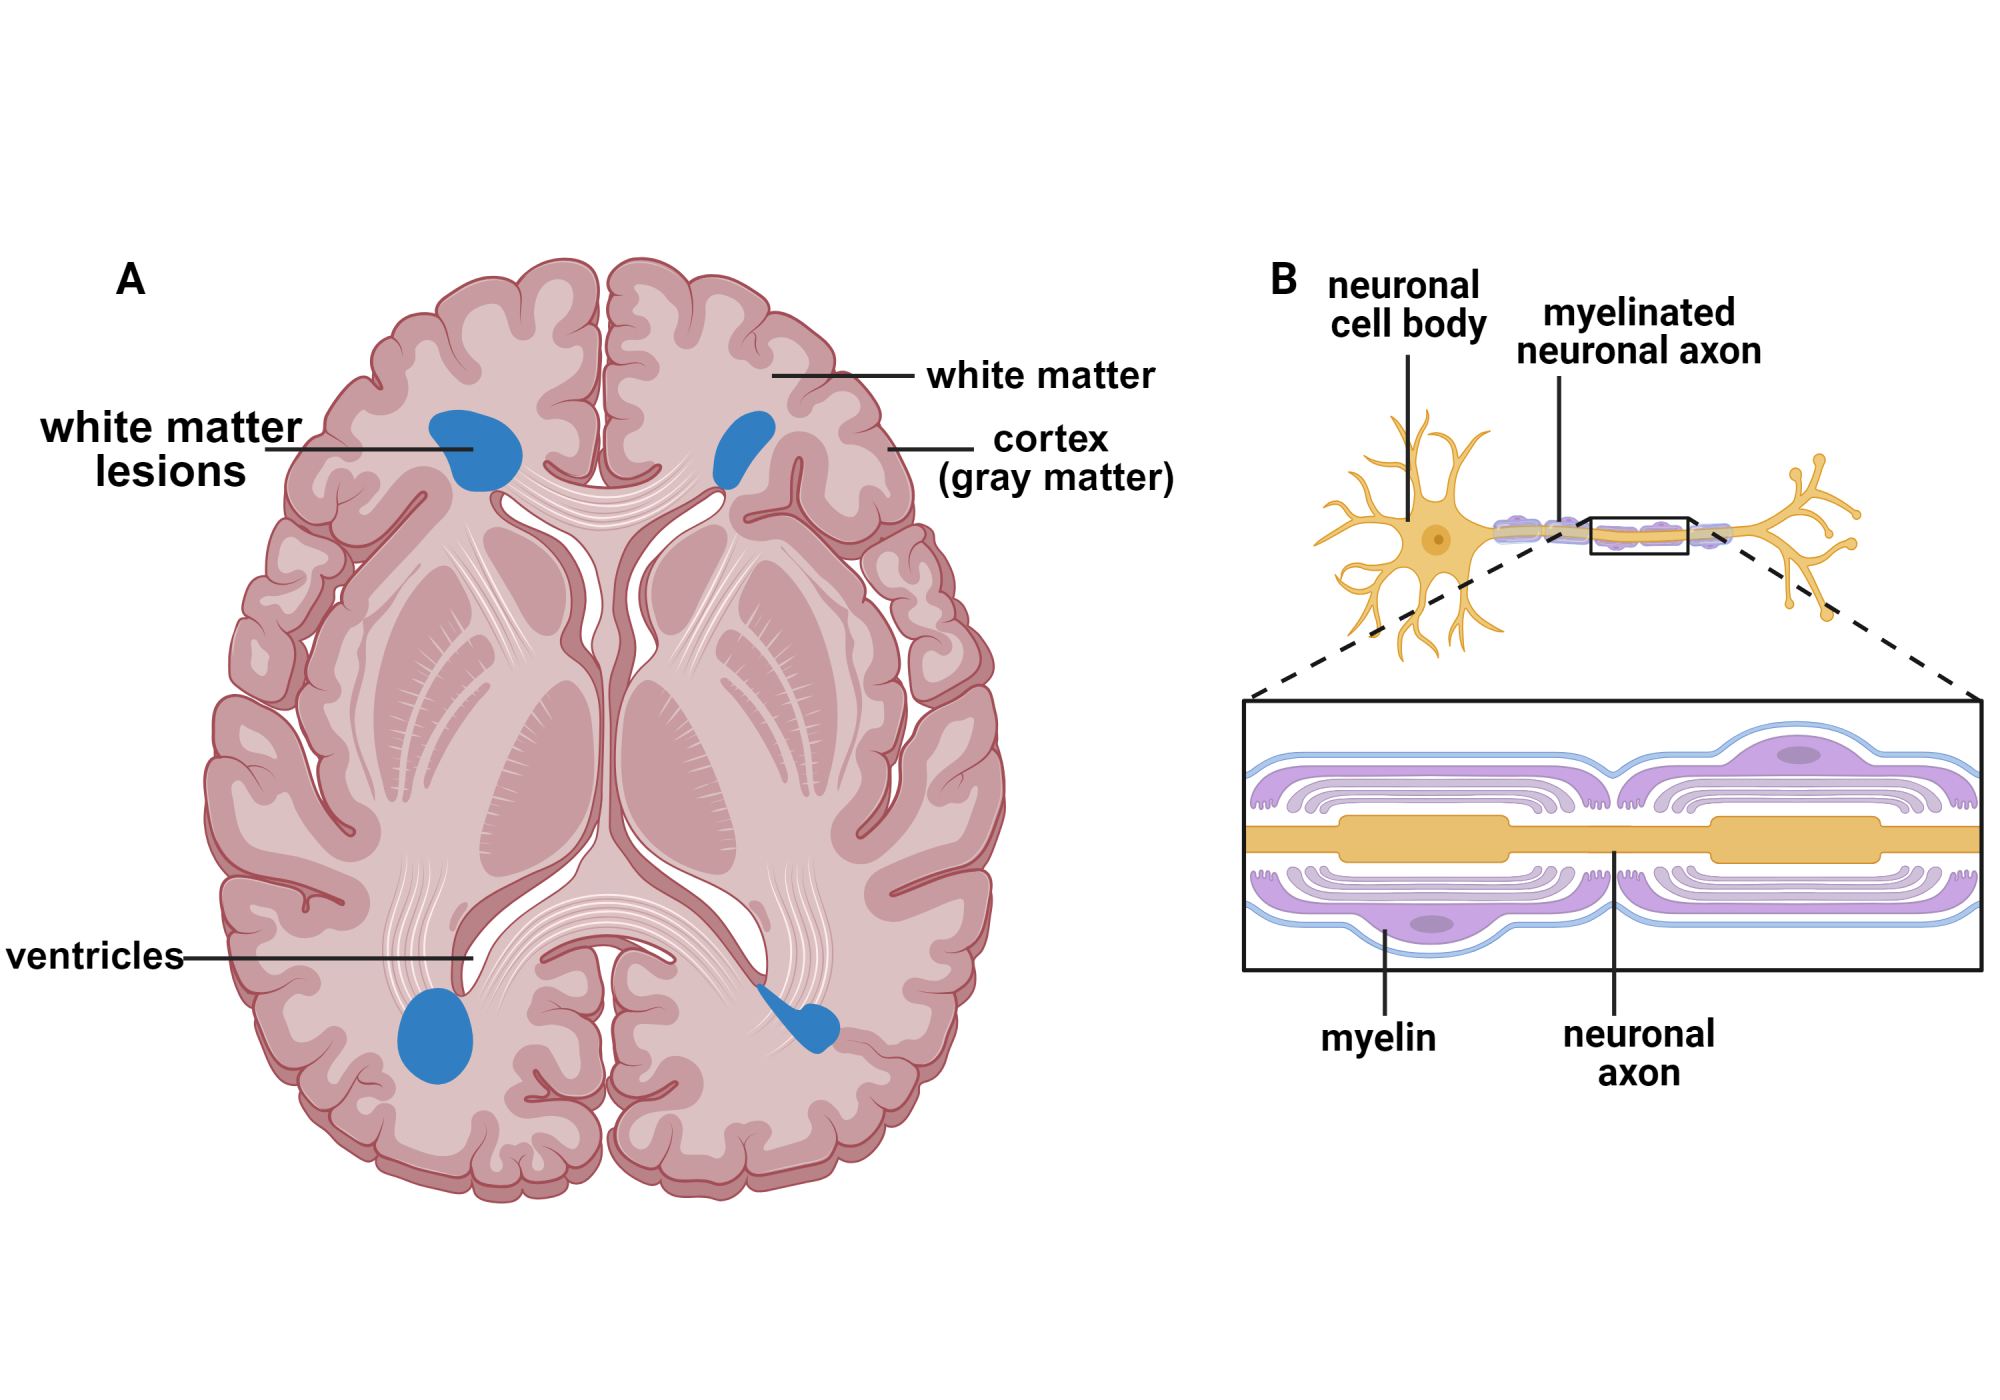

What is the link between white matter lesions and neurodegeneration

Gray Matter vs White Matter Technology Networks new arrivals, Grey Matter vs White Matter in the Brain new arrivals, Brain Anatomy and How the Brain Works Johns Hopkins Medicine new arrivals, Gray and white matter of the brain MedlinePlus Medical new arrivals, White Matter and Your Brain new arrivals, What Is White Matter In The Brain new arrivals, Grey Matter Brain Damage White vs. Grey Matter Injury new arrivals, Grey and White Matter Physiopedia new arrivals, Brain Structure and Function Headway new arrivals, Neuroanatomy of the brain with respect to white matter inside the new arrivals, Why Is Gray Matter Gray Live Science new arrivals, Gray and white matter Organ Systems MCAT Khan Academy new arrivals, White matter The brain s flexible but underrated superhighway new arrivals, What Is White Matter In The Brain new arrivals, What do grey and white matter in the brain represent new arrivals, On Biology The subway of the brain Why white matter matters new arrivals, Why is the brain called grey matter Quora new arrivals, Grey Matter In The Brain new arrivals, Global hypomyelination of the brain white and gray matter in new arrivals, White matter Wikipedia new arrivals, Heard of the brain s gray matter Here s why the white matter is new arrivals, Gray and white matter new arrivals, Covalent Logic grey anatomy brainy facts about grey matter new arrivals, Unlocking Your Brain White Matter VS Grey Matter Muse EEG new arrivals, What is the link between white matter lesions and neurodegeneration new arrivals, What is new arrivals, Anatomy of the white matter tracts Video Anatomy Osmosis new arrivals, You have likely heard of the brain s gray matter here is why the new arrivals, Gray Matter and White Matter in the Brain new arrivals, neuroscience Why is the order of white grey matter different in new arrivals, 25 Brain facts you should know Brainscape Academy new arrivals, White Matter Wonders Re imagining the Brain s Silent Majority new arrivals, Vascular dementia explained Alzheimer s Research UK new arrivals, Volume of gray brain matter significantly lower in people with new arrivals, Even Mild Cases Of COVID 19 Can Leave A Mark On The Brain Such As new arrivals.

Gray Matter vs White Matter Technology Networks new arrivals, Grey Matter vs White Matter in the Brain new arrivals, Brain Anatomy and How the Brain Works Johns Hopkins Medicine new arrivals, Gray and white matter of the brain MedlinePlus Medical new arrivals, White Matter and Your Brain new arrivals, What Is White Matter In The Brain new arrivals, Grey Matter Brain Damage White vs. Grey Matter Injury new arrivals, Grey and White Matter Physiopedia new arrivals, Brain Structure and Function Headway new arrivals, Neuroanatomy of the brain with respect to white matter inside the new arrivals, Why Is Gray Matter Gray Live Science new arrivals, Gray and white matter Organ Systems MCAT Khan Academy new arrivals, White matter The brain s flexible but underrated superhighway new arrivals, What Is White Matter In The Brain new arrivals, What do grey and white matter in the brain represent new arrivals, On Biology The subway of the brain Why white matter matters new arrivals, Why is the brain called grey matter Quora new arrivals, Grey Matter In The Brain new arrivals, Global hypomyelination of the brain white and gray matter in new arrivals, White matter Wikipedia new arrivals, Heard of the brain s gray matter Here s why the white matter is new arrivals, Gray and white matter new arrivals, Covalent Logic grey anatomy brainy facts about grey matter new arrivals, Unlocking Your Brain White Matter VS Grey Matter Muse EEG new arrivals, What is the link between white matter lesions and neurodegeneration new arrivals, What is new arrivals, Anatomy of the white matter tracts Video Anatomy Osmosis new arrivals, You have likely heard of the brain s gray matter here is why the new arrivals, Gray Matter and White Matter in the Brain new arrivals, neuroscience Why is the order of white grey matter different in new arrivals, 25 Brain facts you should know Brainscape Academy new arrivals, White Matter Wonders Re imagining the Brain s Silent Majority new arrivals, Vascular dementia explained Alzheimer s Research UK new arrivals, Volume of gray brain matter significantly lower in people with new arrivals, Even Mild Cases Of COVID 19 Can Leave A Mark On The Brain Such As new arrivals.